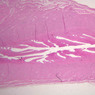

The endometrium of the cervical canal does not slough during the menstrual phase. The glands in this region are relatively large and extensively branched. They are lined by a tall simple columnar epithelium very active in the secretion of mucus. Occasionally these glands become blocked forming Nabothian cysts. The transition of the epithelium of the cervix to that of the vagina is abrupt and is in the region of the external os. At this point, the cervical simple columnar is replaced by the vaginal stratified squamous epithelium (slide B-98 [2.5x-labeled, 10x, 20x, 40x] [2.5x, 10x, 20x, 40x]). This is an area which is commonly inflamed as well as a primary location of cervical cancer.